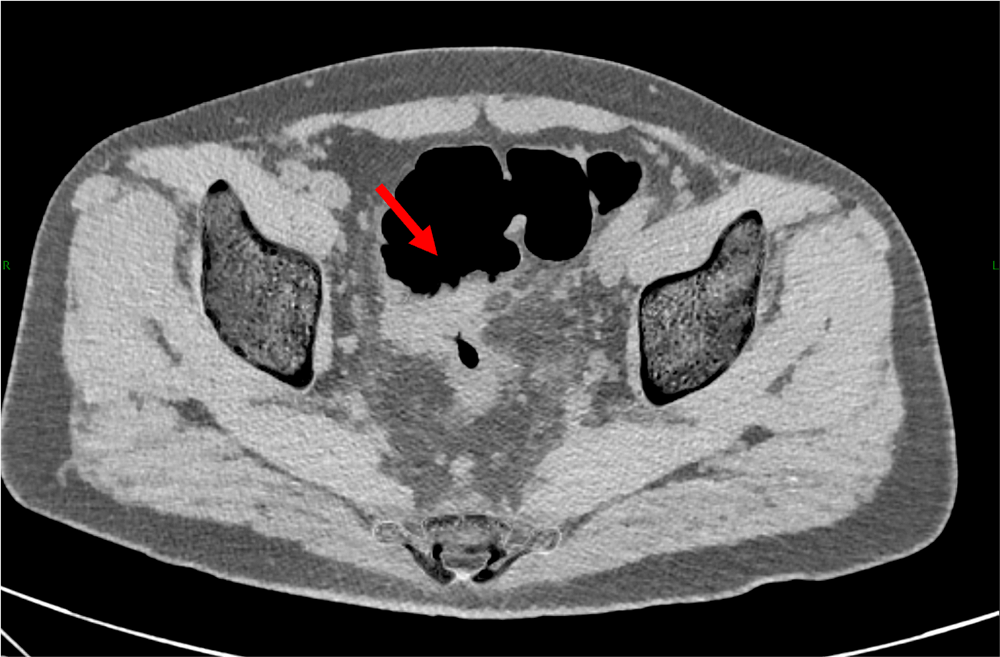

図2.単純(Calcium Suppression画像)、水平断

ガストログラフィンの高吸収が消失しており、辺縁が明瞭に描出されている。

本症例では、高度狭窄を呈した進行直腸癌に対して造影CTC検査を施行した。検査前には、腸管内病変の視認性を向上させる目的で、ガストログラフィンを経口投与している。そのため大腸内の貯留物は高吸収となっているが、物質密度画像(material density image:MDI)を作成することにより、病変の辺縁の描出は問題なく施行できている。